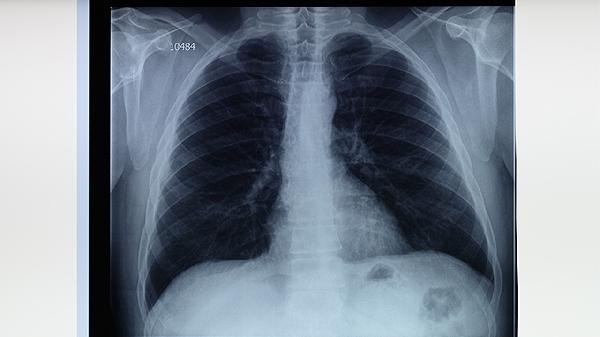

肺結(jié)核治療方法介紹

肺結(jié)核可通過(guò)藥物治療、手術(shù)治療、營(yíng)養(yǎng)支持、隔離防護(hù)、心理疏導(dǎo)等方式治療。肺結(jié)核通常由結(jié)核分枝桿菌感染引起,主要表現(xiàn)為咳嗽、咳痰、發(fā)熱、盜汗等癥狀。1、藥物治療肺結(jié)核藥物治療需遵循早期、聯(lián)合、適量、規(guī)律、全程原則。常用一線抗結(jié)核藥物包括異煙肼片、利福平膠囊、吡嗪酰胺片、乙胺丁醇片等。異煙肼片可抑制結(jié)核菌細(xì)胞壁合成,利福平膠囊能阻斷細(xì)菌RNA合成,吡嗪酰胺片對(duì)酸...